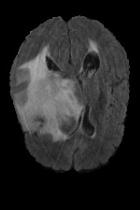

Current unsupervised anomaly localization approaches rely on generative models to learn the distribution of normal images, which is later used to identify potential anomalous regions derived from errors on the reconstructed images. However, a main limitation of nearly all prior literature is the need of employing anomalous images to set a class-specific threshold to locate the anomalies. This limits their usability in realistic scenarios, where only normal data is typically accessible. Despite this major drawback, only a handful of works have addressed this limitation, by integrating supervision on attention maps during training. In this work, we propose a novel formulation that does not require accessing images with abnormalities to define the threshold. Furthermore, and in contrast to very recent work, the proposed constraint is formulated in a more principled manner, leveraging well-known knowledge in constrained optimization. In particular, the equality constraint on the attention maps in prior work is replaced by an inequality constraint, which allows more flexibility. In addition, to address the limitations of penalty-based functions we employ an extension of the popular log-barrier methods to handle the constraint. Comprehensive experiments on the popular BRATS'19 dataset demonstrate that the proposed approach substantially outperforms relevant literature, establishing new state-of-the-art results for unsupervised lesion segmentation.